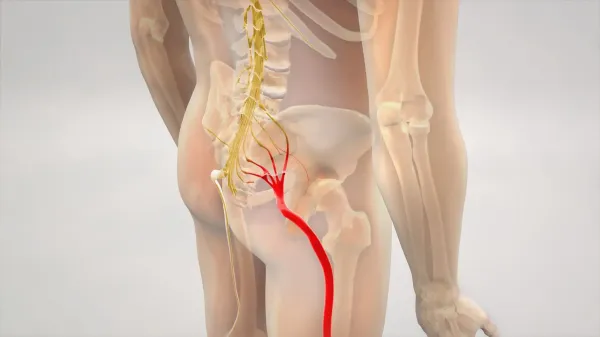

Ako dlho trvá ischias?

Trvanie ischiasu zvyčajne závisí od typu a závažnosti základného problému. Zatiaľ čo ischias zvyčajne ustúpi v priebehu niekoľkých týždňov, niektoré zdravotné stavy môžu spôsobiť, že vaše príznaky… Viac

Pochopenie symptómov ischiasu: mravčenie, necitlivosť, mrznutie a pálenie

Symptómy ischiasu sú veľmi variabilné kvôli mnohým zložitým a prepleteným nervovo súvisiacim prvkom, ktoré sú zahrnuté. Príklady toho, ako ľudia opisujú symptómy, sa pohybujú od: Pocit mravčenia,… Viac

Každodenné aktivity na zmiernenie ischiasu (zápal sedacieho nervu)

Úprava polohy a pohybových aktivít môžu pomôcť kontrolovať bolesť spôsobenú dráždením ischiasu tým, že uvoľní tlak na nervy a mäkké tkanivá v dolnej časti chrbta. Tieto úpravy môžu tiež pomôcť… Viac